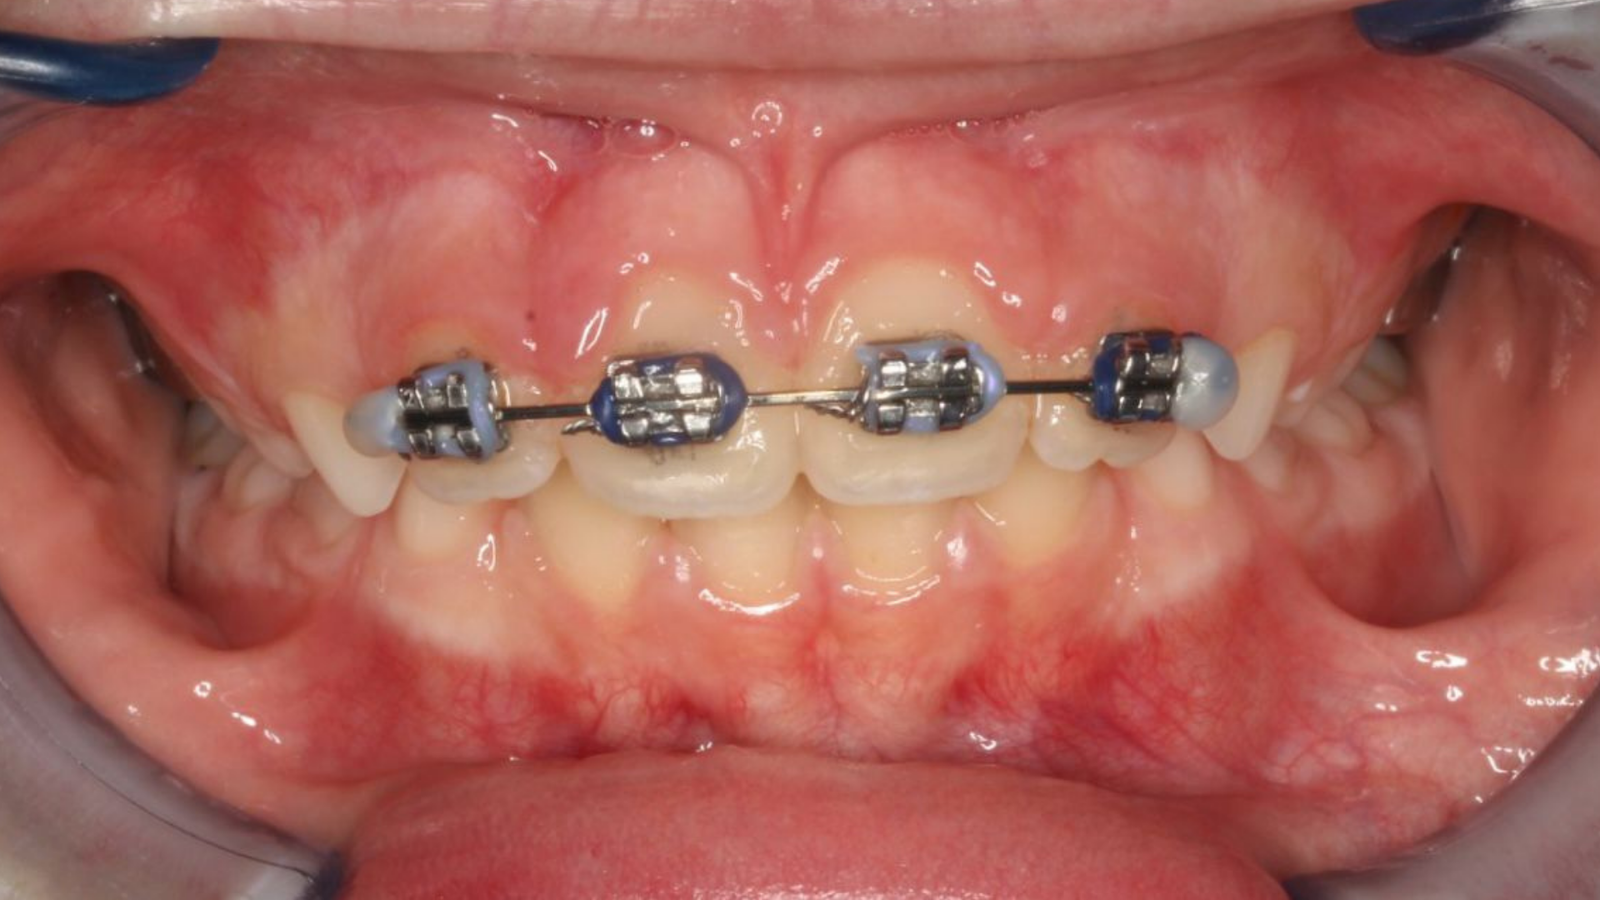

con ortopedia y ortodoncia, paso a paso.